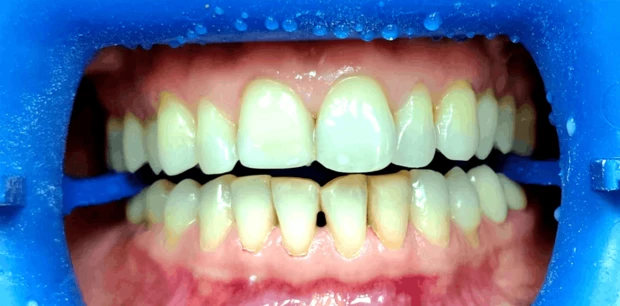

Ортодонтия

Исправление прикуса и выравнивание зубов брекет-системой

Пациент У., 15 лет. Родители обратились с жалобами на неровные зубы сына. Проведено ортодонтическое лечение брекет-системами. Лечение проводилось 2 года.